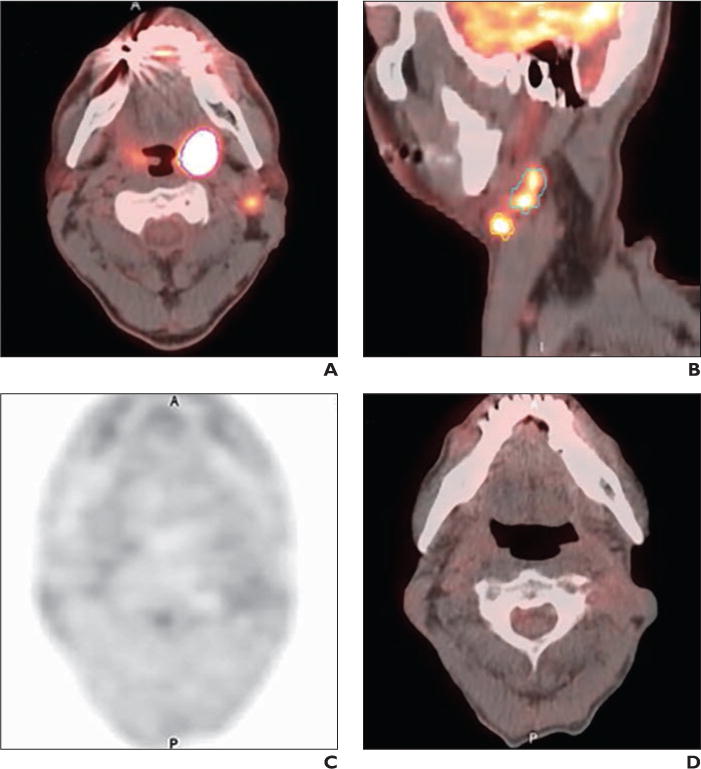

Fig. 4.

55-year-old man with history of stage IV (T2N2bM0) human papillomavirus–positive squamous cell carcinoma of left tonsil and left level IIA nodes.

A and B, Axial (A) and sagittal (B) fused PET/CT baseline images yielded low total metabolic tumor volume of 18 mL. Left tonsillar primary is outlined in magenta; larger left IIA node is outlined in green; and smaller left IIA node is outlined in yellow.

C and D, No recurrence is evident on subsequent PET (C) and fused PET/CT (D) images at 48-month follow-up after treatment with definitive chemoradiation (cisplatin and radiotherapy to total dose of 70 Gy with good response).

A = anterior; P = posterior.